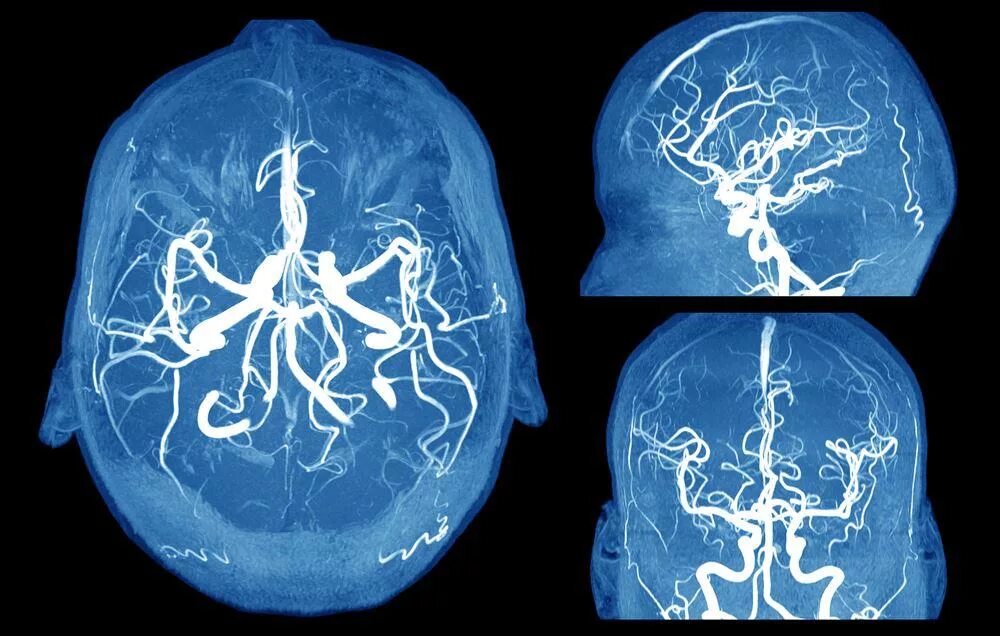

Аневризма сосудов мозга симптомы